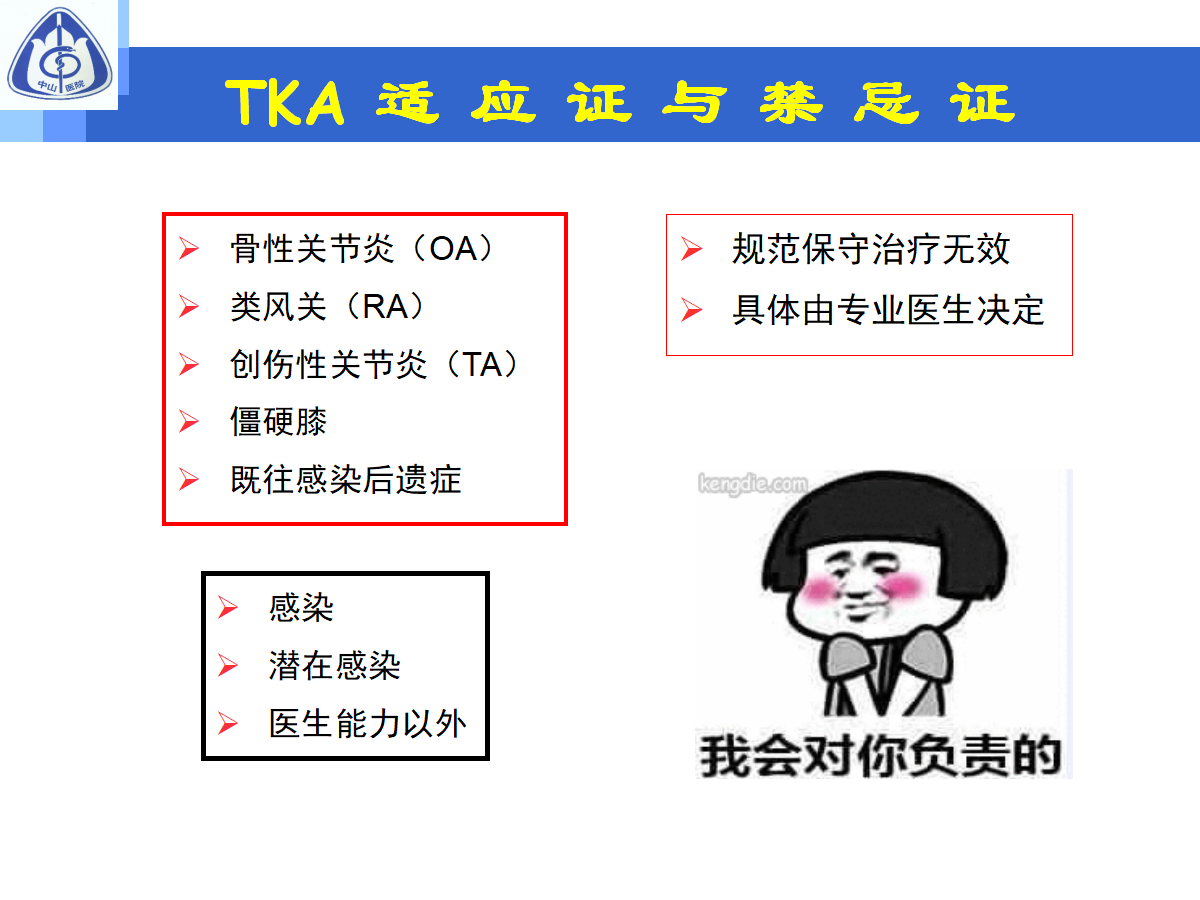

Tka 禁忌

人工全膝关节置换术 医栈文章

人工全膝关节置换术ppt课件 图文 百度文库

人工全膝关节置换术介绍